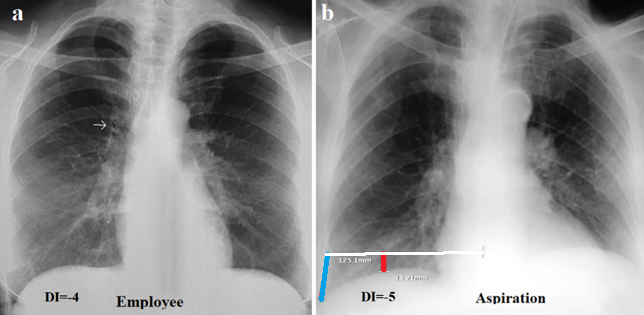

In 20 patients of the 3rd group, there were cases of acute bronchitis-bronchiolitis, which led to inflammation of the mucous membrane of the bronchi and bronchioles, creating an obstruction for breathing with a decrease in tidal volume. In some patients, the cause of inflammation was a viral infection, and in others, inflammation was caused by hydrochloric acid during aspiration (Figure 4). In acute obstructive bronchitis-bronchiolitis, a moderate increase in lung volume was observed. DI ranged from -3 to - 6 cm (mean -5.2 cm).

Figure 4. Radiographs of patients with acute obstructive pulmonary disease. (a) Bronchitis-bronchiolitis due to viral infection. The lung roots are enlarged and structureless. Thickened walls of the main bronchi are shown by the arrow on the right. Increased pulmonary markings in the lower fields. Deep sinuses are open. DI=-4. (b) Condition after clinically confirmed aspiration. Marked increase in pulmonary markings in the lower field on the right. The pulmonary roots are dilated and structureless. The volume of the right lung is increased. DI=-5.